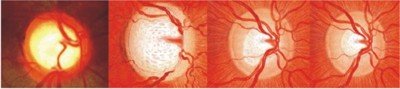

اِس معائنے میں سب سے اہم چیز C:D ratio کا معائنہ ہے ۔ یہ معائنہ بہت اہمیّت رکھتا ہے ۔ آ پٹک ڈسک [Optic disc] عمومی طور پر گلابی رنگ کی ہوتی ہے جبکہ اُس کا مرکزی حصّہ سفید رنگ کا ہوتا ہے جِسے آپٹک کپ کہتے ہیں۔ ان دونوں کے باہمی تناسب کا معائنہ کیا جاتا ہے ۔ اگر ایک تہائی حصہ سفید باقی سارا گلابی ہو تو یہ نارمل ہے۔ اسے 0.3 کہا جاتا ہے۔ کالا موتیا کی اِس قسم میں یہ تناسب برقرار نہیں رہتا اور آہستہ آہستہ سفید حصہ بڑا ہوتا جاتا ہے اور گلابی حصہ چھوٹا ہوتا جاتا ہے جب یہ آدھا آدھا ہو جاتا ہے تو 0.5 کہا جاتا ہے۔ جب گلابی حصہ صرف 10% فیصد رہ جائے تو 0.9 کہا جاتا ہے نیچے تصویر میں اس کی مختلف کیفیات کو دکھایا گیا ہے ۔